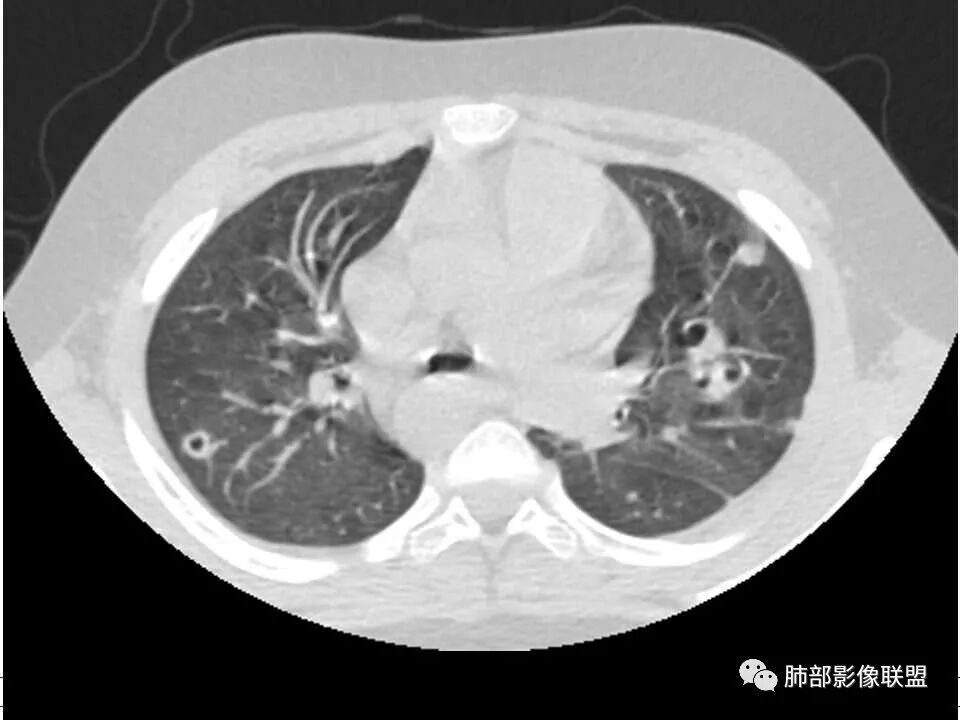

患者儿童,因右下肢疼痛伴肿胀14天就诊。病程中有发热及伴随症状。膝关节MRI提示右侧膝关节及右髌骨髁异常信号影,右膝髌上囊及关节腔内少量积液。胸部CT:双肺胸膜下多发结节影,部分结节空洞形成,且结节周围可见血管集束征。综合考虑血源性脓毒性肺栓塞、坏死性肺炎。右侧骨髓炎、血播性金葡菌肺炎,鉴别其他特殊感染及血管炎。

发热,下肢肿胀骨髓水肿,骨髓炎可能;双肺多发结节,部分空洞,左下肺胸膜下楔形阴影,考虑感染性病变,肺梗死;上腔静脉、奇静脉增宽,肝大,考虑股部深静脉拴子进入体循环及肺动脉,综上考虑下肢骨髓炎,深静脉脓毒栓子,肺部感染并肺栓塞

男,8岁,两肺多发随机分布结节空洞影,壁光整,考虑血道来源,结合右侧膝关节有骨髓水肿信号,临床感染指标明显增高,考虑骨髓炎并血道播散,金葡菌感染?LCH小孩骨头症状相对较轻,放在代排吧。

小儿,急性起病,下肢疼痛,mr提示骨髓水肿,临床化验炎性指标高,考虑金葡菌骨髓炎,双肺多发结节,以血管支气管束及胸膜下分布为主,部分结节近端与血管相连,部分结节可见空腔,内壁光整,部分囊腔有张力,考虑骨髓炎并肺内血播感染,金葡?

儿童,发热,急性起病,右下肢骨水肿,两肺弥漫性病变,伴囊,胸膜下分布,部分呈楔形,血道分布,符合金葡菌感染,脓毒肺栓塞

2.双肺多发片影,随机分布,多空洞或囊腔,胸膜下多楔形影,气道未见受累等等符合脓毒血症影像学表现,尤其是金葡。

4.急性骨髓炎多为血源性感染,金葡菌感染居多,好发于血供丰富而流速相对缓慢的干骺端,在儿童因骺软骨阻挡而较少蔓延至骨骺及关节腔(关节腔常有反应性积液),脓腔高张力加之沿哈氏管(Haversian canal)及骨膜下蔓延易于导致骨组织缺血坏死。及时开窗引流有助于防止病情恶化或迁延。

2、脓肿:实变区内脓肿,最常见吸入性金葡菌引起的多,下叶多见,在实变区中央,外壁不清,内壁光滑,可见气液平面;血源性脓肿,多发,结节状,大小无差异,边清,光滑,壁薄;